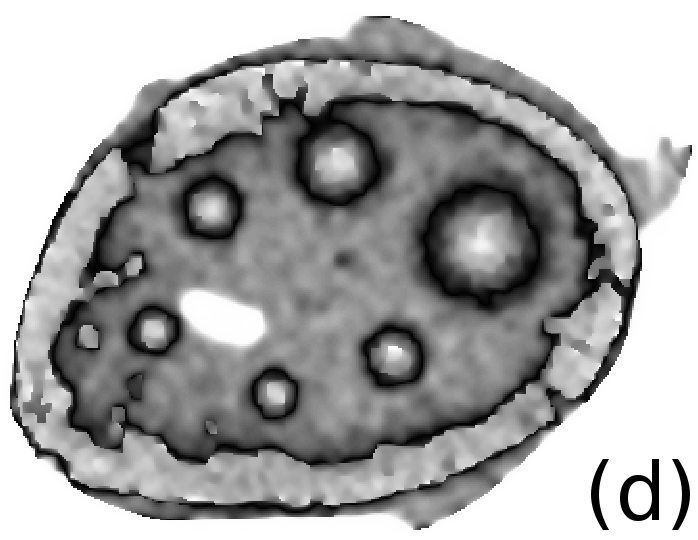

To simulate emission tomography reconstruction we designed a more realistic phantom from the high-quality X-ray scan of a mice bone. The data was acquired on a Nikon Metris Custom Bay cone-beam scanner at the Henry Moseley Manchester X-ray facility, and was reconstructed with the Feldkamp algorithm (see Fig. 7 (left)). We thresholded the obtained reconstruction and added six gaussians with various kernel widths (see Fig. 7 (middle and right)).

To simulate PET projection data we used NiftyRec [22], a software for tomographic reconstruction, providing GPU-accelerated reconstruction for emission and transmission computed tomography. The phantom size is pixels and 300 projections was simulated. Poisson noise was added to projections with an expected number of photon counts in total. Twenty noise realizations were simulated to estimate methods quantitatively. The point spread function of the PET system was modelled (with convolution of the sinogram columns with a Gaussian of full width half maximum of three pixels) in the projection and back-projection operations. No scatter was simulated in this study. For our experiments (see algorithm 2) we performed 130 MLEM iterations and 5 inner iterations (denoising step).

To quantify obtained reconstructions we used averaged over all noise realizations RMSE (23) values in the bone region (BR) and in Gaussian regions (GR). All regularization parameters were carefully selected by comparing the mean of all RMSE values over all noise realizations in GR and BR (see Fig. 8).

After estimation of regularization parameters we performed twenty reconstructions for each method with various Poisson noise distributions. The mean values for GR and BR over all noise realizations are shown in Fig. 9. This result proves that the EL penalty is very successful in resolving smooth features (six Gaussians in this case) and also quite competitive for the BR (lower RMSE value than for TV).

In Fig. 10 and 11 one can notice that the BR is very smooth for TV and TV- penalties and some long-wave oscillations can be seen in the reconstructed image with EL penalty. This result corresponds to the expected behaviour of the EL penalty. We note here that the phantoms background (see Fig. 7) is not as flat as TV and TV- penalty recovered it. Furthermore, a small size dot-like feature (approximately in the centre of the phantom) is almost smoothed out with TV and TV- recovery. However, it is visible and well recovered with EL penalty. The sharp features, overall, are reconstructed very well with MLEM-EL method and seem even sharper compare to other methods (see the bone outer rim in Fig 10).